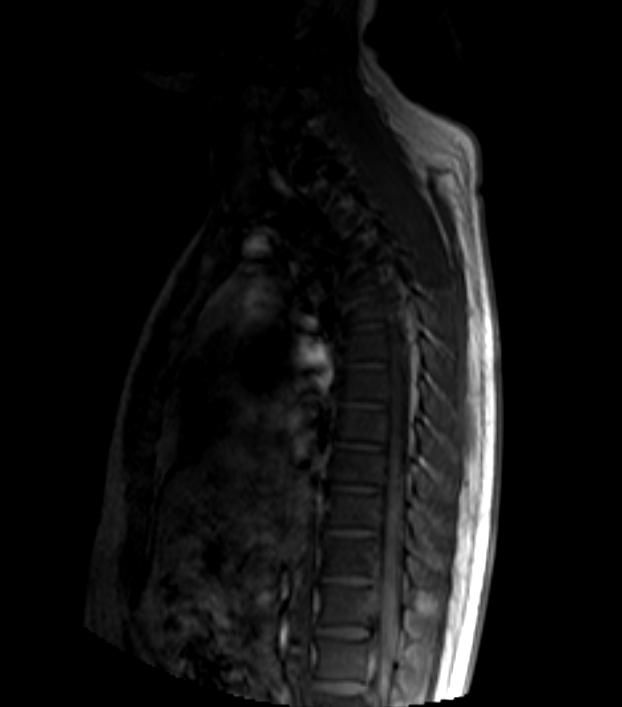

• 우선 이 영상은 T2 강조 시상면(sagittal) MRI 영상으로 보이며, 전체 척추를 한 번에 촬영한 전척추(whole spine) 스크리닝 영상으로 판단됩니다.

말씀하신 "상체 부분 중간의 하얀 음영"은 흉추(thoracic spine) 부위에서 보이는 T2 고신호(high signal intensity) 병변으로 보입니다. T2 영상에서 밝게 보인다는 것은 해당 부위에 수분 함량이 높은 조직이 있다는 의미인데, 이것이 곧 악성 병변을 의미하지는 않습니다.

가능한 감별 진단을 말씀드리면, 우선 가장 흔한 원인은 추간판(intervertebral disc) 내의 수분 변화 혹은 Schmorl's node처럼 양성 구조적 변화입니다. 그 외에 혈관종(vertebral hemangioma)은 척추에서 매우 흔하게 발견되는 양성 종양으로, T2에서 밝게 보이는 전형적인 소견을 보입니다. 척추 혈관종은 성인의 10퍼센트 이상에서 우연히 발견될 만큼 흔하며 대부분 치료가 필요 없습니다.

물론 영상 한 장만으로 확정적인 판독은 어렵고, 전체 시퀀스(T1, T2, 조영증강 여부 등)와 임상 증상을 함께 고려해야 정확한 판단이 가능합니다.